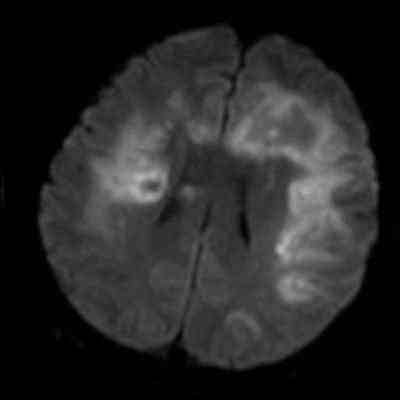

- Bilateral asimetrik subkortikal ve derin beyaz cevherde T1 ağırlıklı görüntülerde belirgin hipointens (oklar), T2A görüntülerde hiperintens (oklar), gri cevhere bakan kesimi düzgün (oklar), DAG’de hiperintens (ok) lezyonlar izlendi. Lezyonlarda T2/FLAIR uyumsuzluğu vardı (ok). Serebellar beyaz cevherde dentat nukleusu koruyan hilal işareti görüldü (ok başı). SWI sekansta sol motor kortekste hipointens kronik glioinflamatuar reaksiyon ile uyumlu sinyal değişikliği izlendi (ok başı).

- Çoğunlukla subkortikal beyaz cevherde ve U fiberlerde, asimetrik, genelde kitle etkisi yapmayan ve kontrastlanmayan demiyelinizan lezyonlar görülür. Korteks ve derin gri cevher tutulumu daha nadirdir.

- PML lezyonları, T1A görüntülerde belirgin hipointenstir. Gri cevhere bakan yüzleri keskin olup T2/FLAIR uyumsuzluğu önemli özelliğidir.